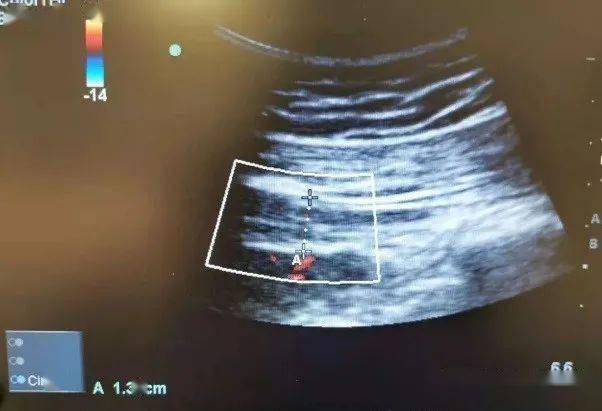

医生为患者调整了药物,并进行了两次颊针治疗。在第二次颊针治疗后,超声影像能明显看到患者的梨状肌厚度减小(图2),说明肌肉痉挛得到了缓解,神经卡压得到解除。B女士在两次治疗后疼痛得到明显缓解,运动不再受限,睡眠也恢复了正常。

图2:治疗后右侧梨状肌厚度1.31cm